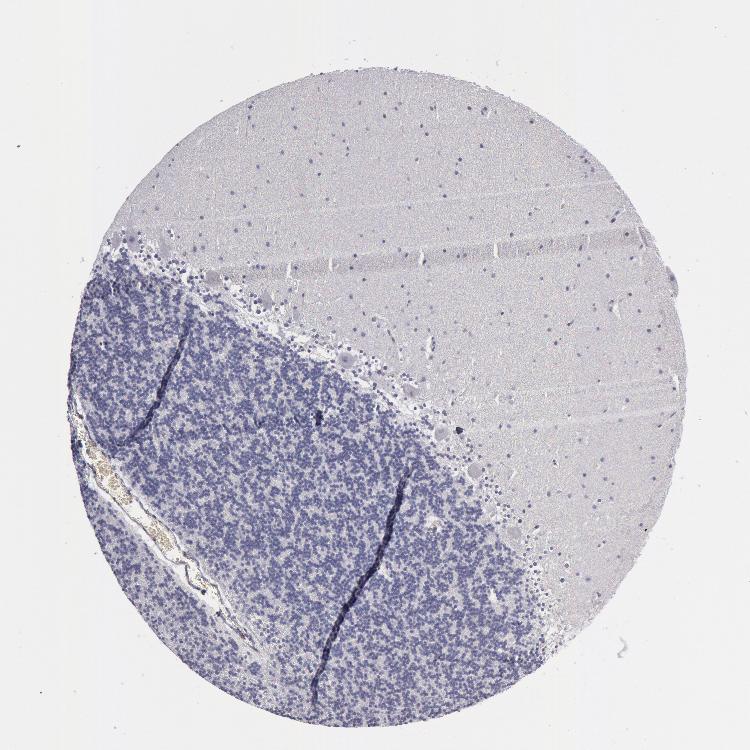

CEREBELLUM - Antibody stainingi

Antibody staining in the annotated cell types in the current human tissue is reported as not detected, low, medium, or high, based on conventional immunohistochemistry profiling in selected tissues. This score is based on the combination of the staining intensity and fraction of stained cells.

Each image is clickable and will lead to virtual microscopy that enables deeper exploration of all samples and also displays staining intensity scores, fraction scores and subcellular localization as well as patient and tissue information for each sample.

Antibody HPA001500

Purkinje cells Not detected

Cells in granular layer Not detected

Cells in molecular layer Not detected